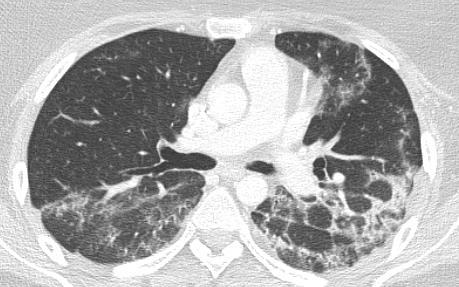

Imaging of Covid 19 infection in children COVID 19 Late

Late

37